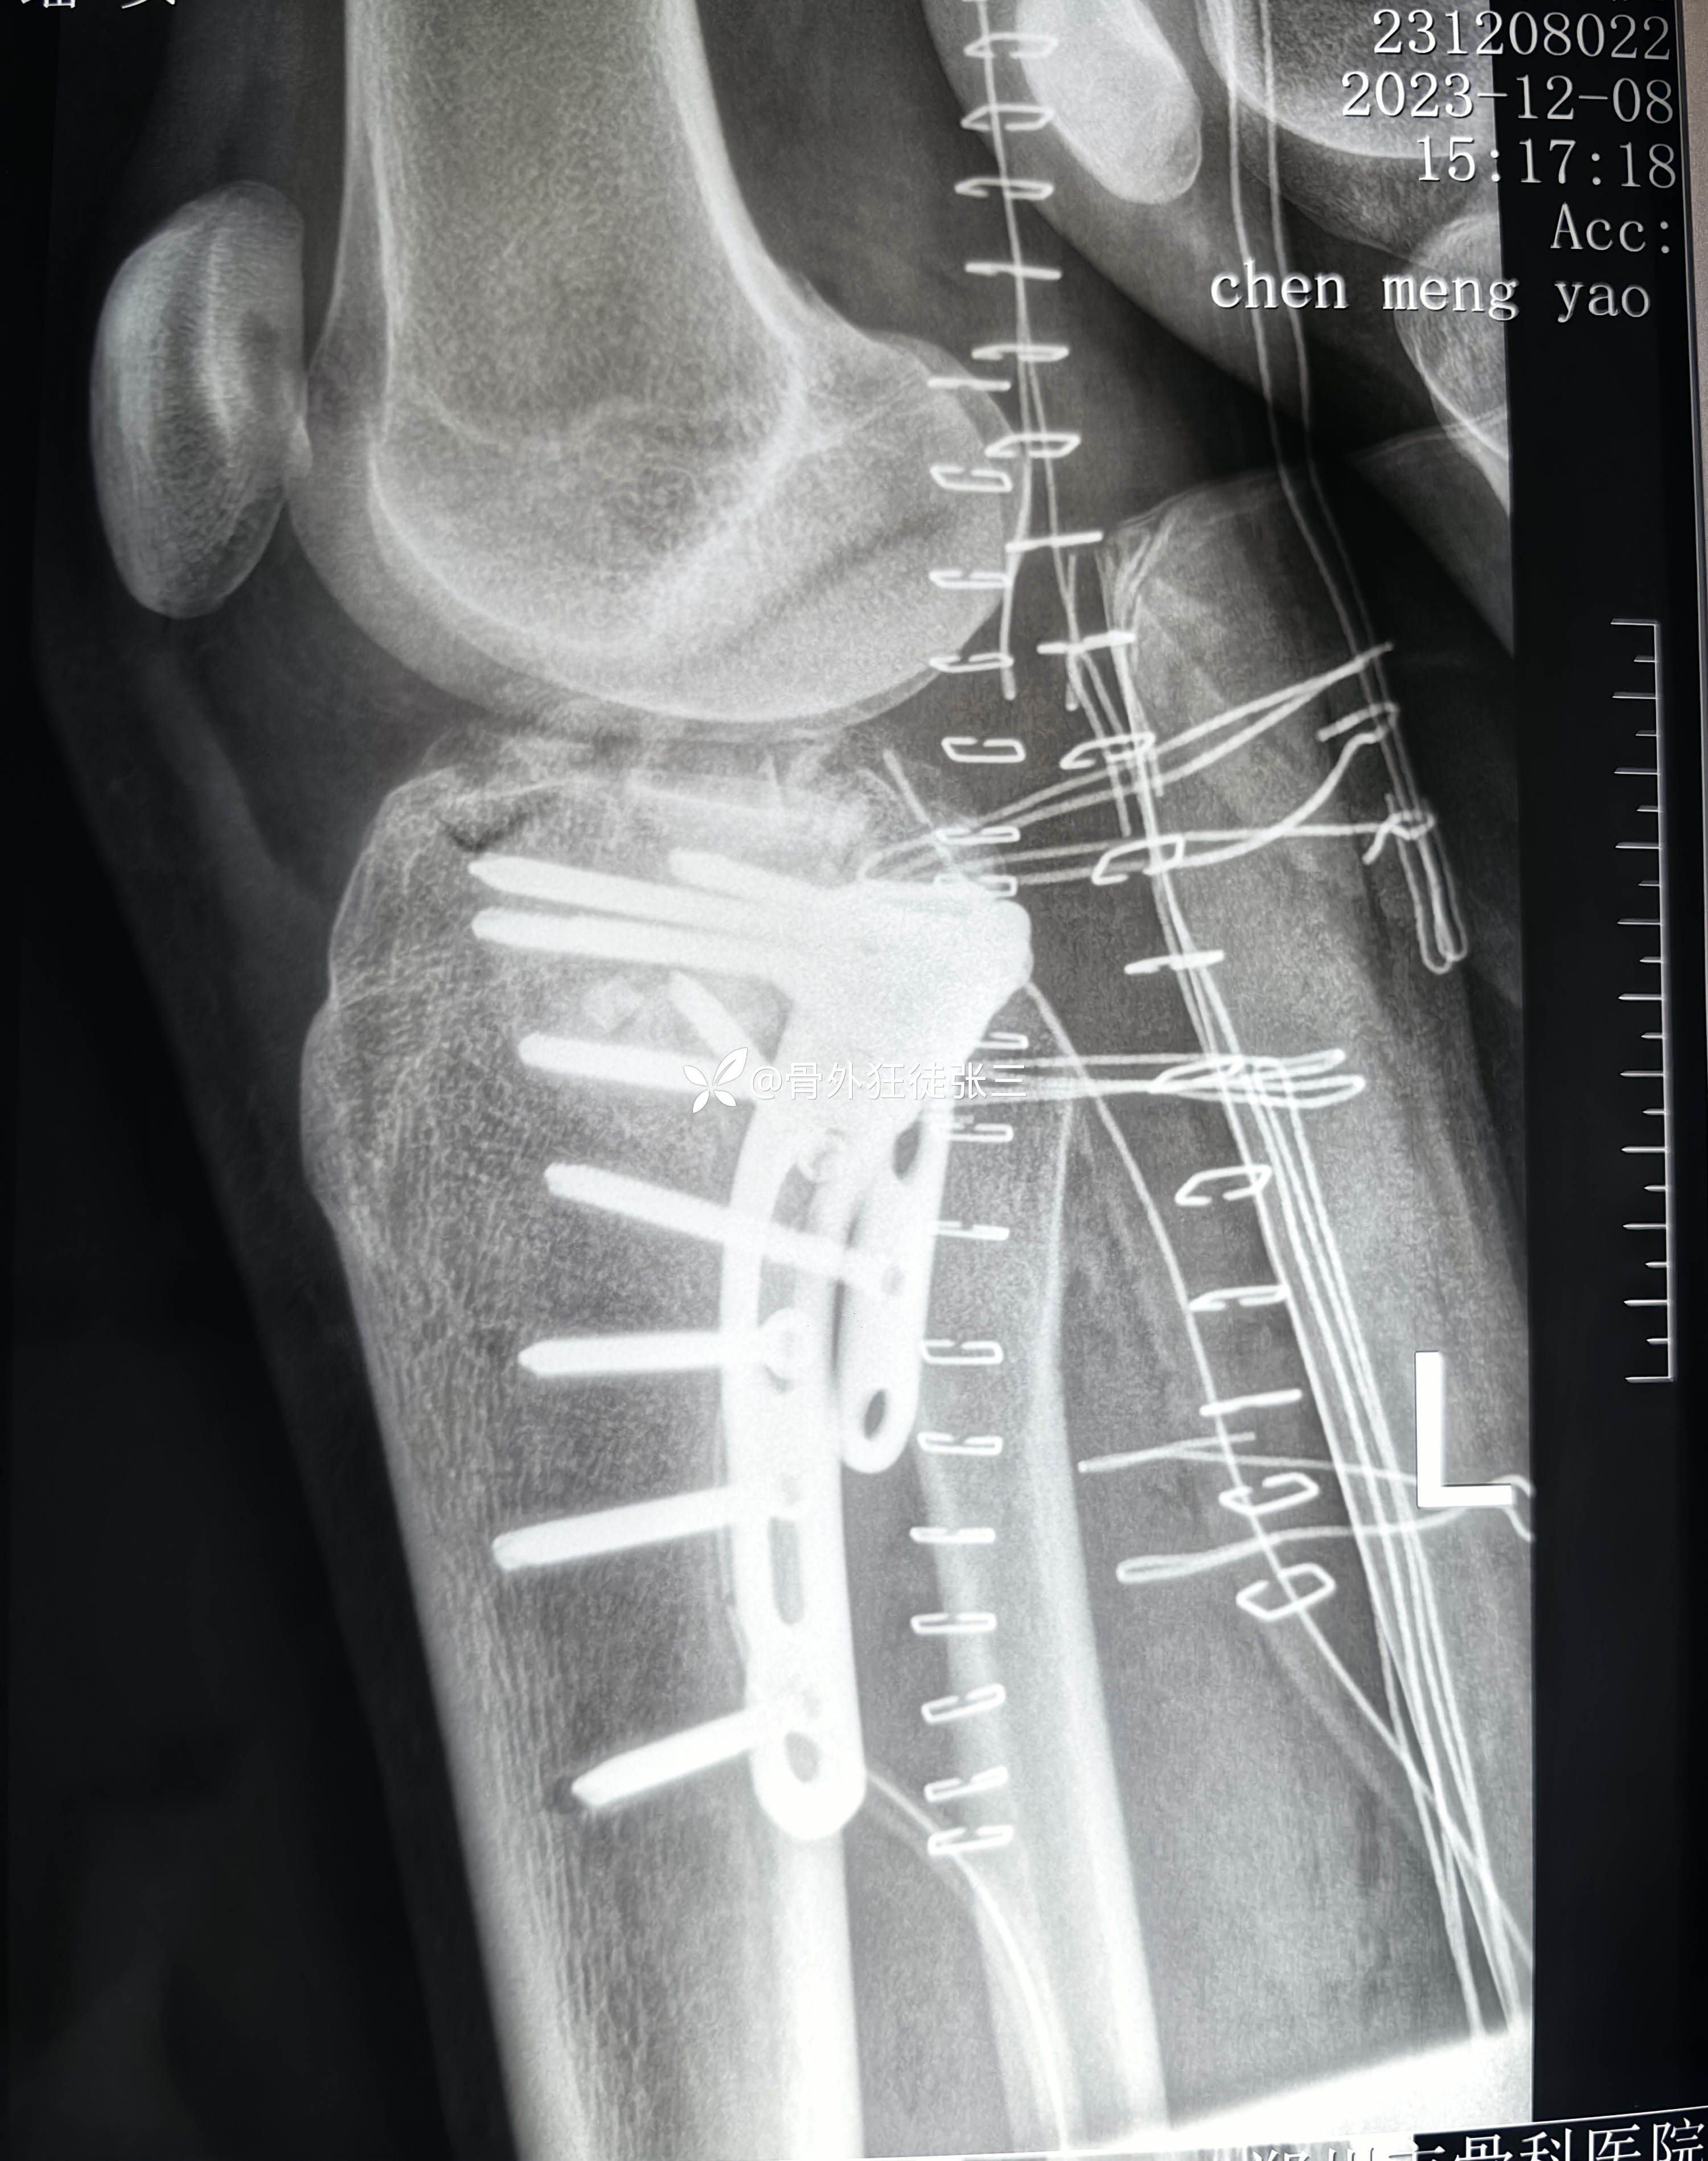

2023.12.08,在当地医院行胫骨平台骨折手术

第一次手术后复查

第二次手术后复查